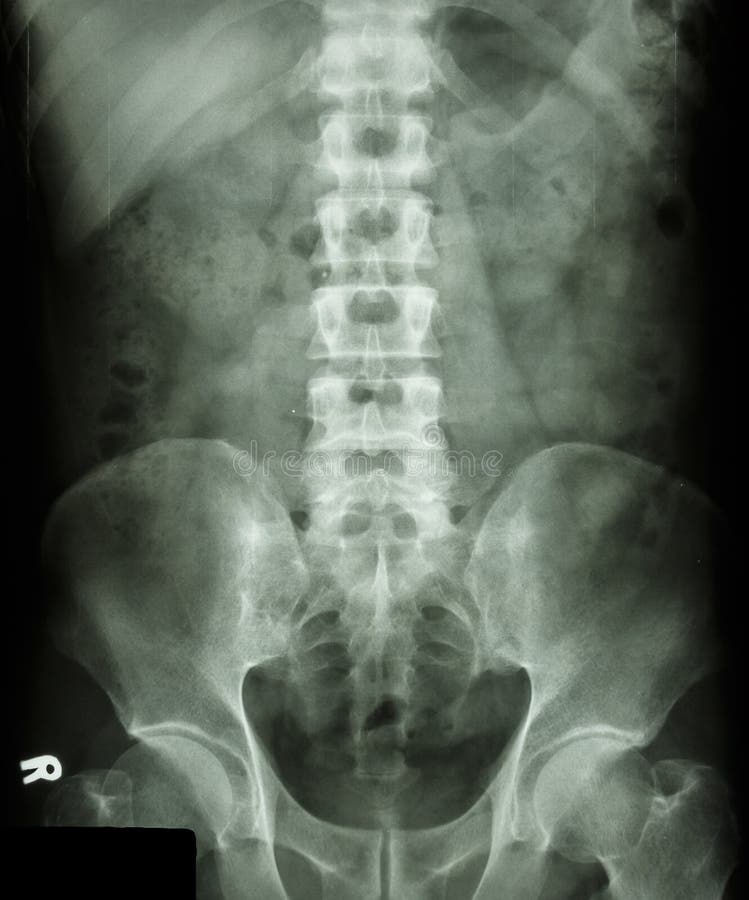

Columna Lumbosacra Ap Y Lat, En qué consiste la radiografía de columna lumbosacra, 1.28 MB, 00:56, 15,031, Madre Teresa Policlinico, 2019-08-08T22:07:58.000000Z, 3, RX COLUMNA LUMBOSACRA AP Y LAT - Activa-T, www.activat.com.co, 800 x 800, jpeg, WebUna Radiografía de la Columna Lumbosacra y Lateral es una imagen de los pequeños huesos (vértebras) en la parte baja de la columna. Esta zona incluye la región lumbar. WebLa articulación lumbosacra y el segmento L5-S1 de la columna vertebral son una fuente común de lumbalgia o ciática. El daño de disco o de articulaciones en el segmento L5. WebColumna lumbosacra y columna total Criterios generales para columna lumbar, que son distintos de la cervical y la dorsal, que seria estructura al centro de la imagen,., 20, columna-lumbosacra-ap-y-lat, Novedades y Muebles WebUna Radiografía de la Columna Lumbosacra y Lateral es una imagen de los pequeños huesos (vértebras) en la parte baja de la columna. Esta zona incluye la región lumbar. WebLa articulación lumbosacra y el segmento L5-S1 de la columna vertebral son una fuente común de lumbalgia o ciática. El daño de disco o de articulaciones en el segmento L5. WebColumna lumbosacra y columna total Criterios generales para columna lumbar, que son distintos de la cervical y la dorsal, que seria estructura al centro de la imagen,.

WebColumna total, bipedestación, AP y LAT; Columna total: test de bending; Mensuración de miembros; Tomografía convencional; Clavícula; Articulación esternoclavicular; Escápula;. WebProcedimiento para obtener una Rx de columna lumbosacra en proyección lateral. El audio original tiene la explicación durante la toma de la radiografía, puede seguir las. WebRX Columna Lumbar 2 Proy. (Ap y Lat) INDICACIONES PARA REALIZARSE EL ESTUDIO de Rayos X, Radiografía, RX: 1) Presentar receta medica el día del estudio donde se. WebLa radiografía de columna lumbar AP y lateral es el primer paso en el algoritmo diagnóstico. También suele iniciar la secuencia diagnóstica en pacientes con síntomas referidos a la. WebRX Columna Lumbosacra 2 Proy. (Ap y Lat.) INDICACIONES PARA REALIZARSE EL ESTUDIO. 1) Presentar receta medica el día del estudio donde se indique la proyección. WebUna Radiografía de la Columna Cervical AP y Lateral puede ayudar a determinar la causa de síntomas tales como dolor del cuello, hombro, la zona superior de la espalda o. WebUna radiografía de la columna lumbosacra es una imagen de las vértebras lumbares y los pequeños huesos (vértebras) en la parte baja de la columna. Indicaciones Se le pide al. WebRx de columna lumbosacra AP, Lat y oblicuas. English translation: X-rays of the lumbosacral column, anteroposterior, Lateral and oblique. Entered by:.

WebLa razón más común para realizar una radiografía de la columna lumbar, es buscar la causa de lumbago. También ayuda en el diagnóstico de lesiones, enfermedades o. WebLas ap y laterales son dos formas de toma de la radiografía. ¿Qué es una radiografía de columna lumbosacra AP y lateral? Una radiografía de la columna. Webcolumna lumbar: anteroposterior (ap) lateral lumbosacra lateral en flexiÓn lateral en extensiÓn oblicua derecha oblicua izquierda anteroposterior (ap) y lateral (2.